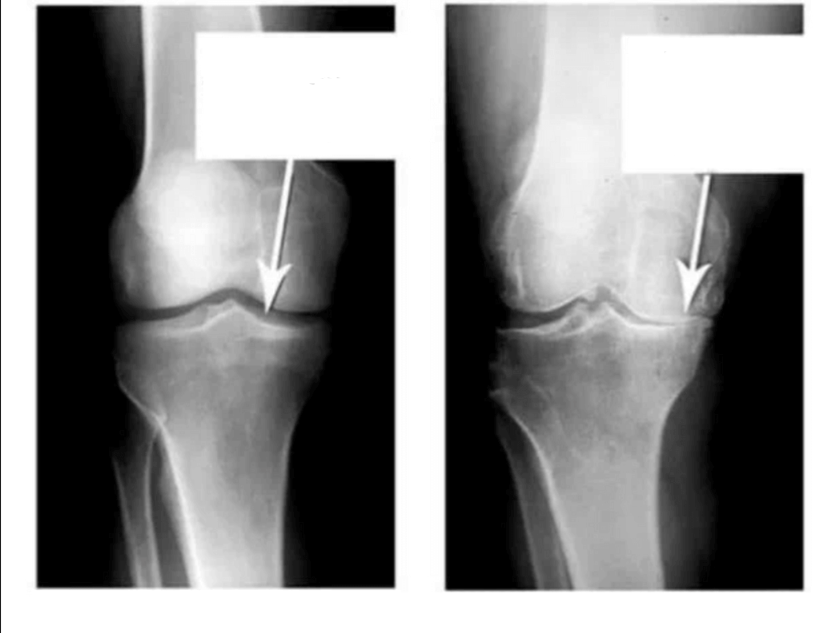

Ба ин суратхо нигаред, мебинед, ки дар расми рост ягон фосилаи бугум вучуд надорад, устухонхо ба хам мемоланд ва боиси дарди сахт мегарданд. Ва боздоштани ин раванд хеле душвор аст! Пас аз чанд сол одам маъюб мешавад ва худро таъмин карда наметавонад.